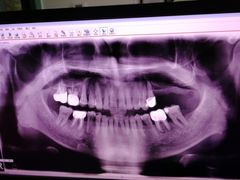

• -上海陈守平口腔诊所

iii | 20-05-16

报错